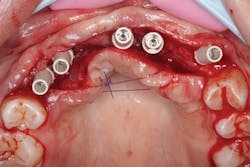

The patient was sedated intravenously in a surgically sterile in-office operatory. The surgical guide was placed over the teeth, checked to make sure it was fully seated without soft tissue impingement or surgical guide excess (figure 5). It was verified that there was no rocking of the guide from either side. An initial pilot drill was made through the guide into the soft tissue. A surgical incision was made with a 15c blade splitting across the keratinized gingiva across the crest of the ridge from Nos. 5–11. A full-thickness flap was elevated buccally and lingually. This released the soft tissue enough to allow the implant drills to go to depth and perform a widening osteotomy. Five osteotomies were made with copious saline irrigation and drill speed of 2,000 rpm. A pilot drill and each sequential step drill guide were used to widen out the osteotomy before placing five 3.5 mm x 10.5 mm MegaGen AnyRidge implants (figure 6). The implants were placed and torqued out at 35 Ncm. (Implants were not placed through the guide, although this was an option. Cover screws were placed. A bone graft with fusion bone binder (figure 7) and platelet-rich fibrin (PRF) were all placed over the implants before suturing with 5.0 polyglycolide sutures (figure 8). The upper partial was relined to take pressure off the soft tissue site.

Figure 6: Implants placed